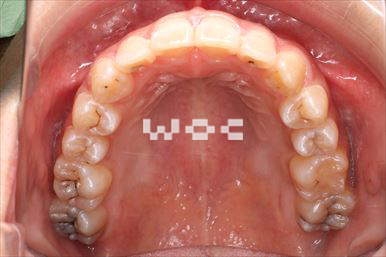

八重歯・叢生上のみ舌側矯正、下はエッジワイズ装置

上は舌側矯正を希望。ガタガタ(叢生)が強い。上顎右側中切歯・側切歯が歯科治療で連結してあったがそれを除去してから治療開始しました。

- 年齢:23歳女性

- 主訴:上下前歯のガタガタが気になる

- 基本矯正料金:103万円

- 治療期間:2年2ヶ月

- 非抜歯